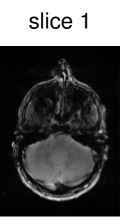

To verify the in-vivo applicability, human brain images of a healthy volunteer were acquired using the above described GRE sequence modified to include the optimized CAIPIRINHA-based pulses. The sequence parameters were set to , , bandwidth , matrix size and FOV . After acquisition, the k-space data of the individual slices were separated using an offline slice-GRAPPA ( coils, kernel size of ) reconstruction [42, 9]. The reference scans used in the slice-GRAPPA reconstruction were performed with the same sequence using an optimized single-slice pulse (not shown here). To decrease the scanning time, we acquired k-space lines ( of the full dataset) around the k-space center for each reference scan. After this separation, a conventional Cartesian reconstruction was performed individually for each slice.

Figure 6 shows the image reconstruction using optimized RF pulses for simultaneous excitation of two, four and six slices with the same slice separation and thickness as above. As can be seen clearly in the first column, all three pulses lead to the desired excitation pattern in-vivo as well. The remaining columns show the slice-GRAPPA reconstructions, which illustrate that the excitation is uniform across the field of view.